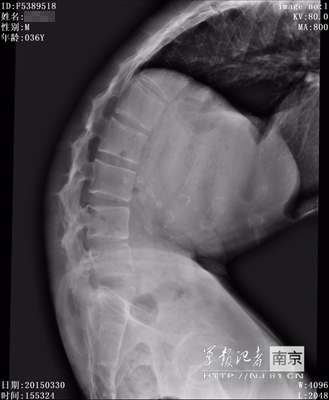

術(shù)前術(shù)后CT對比